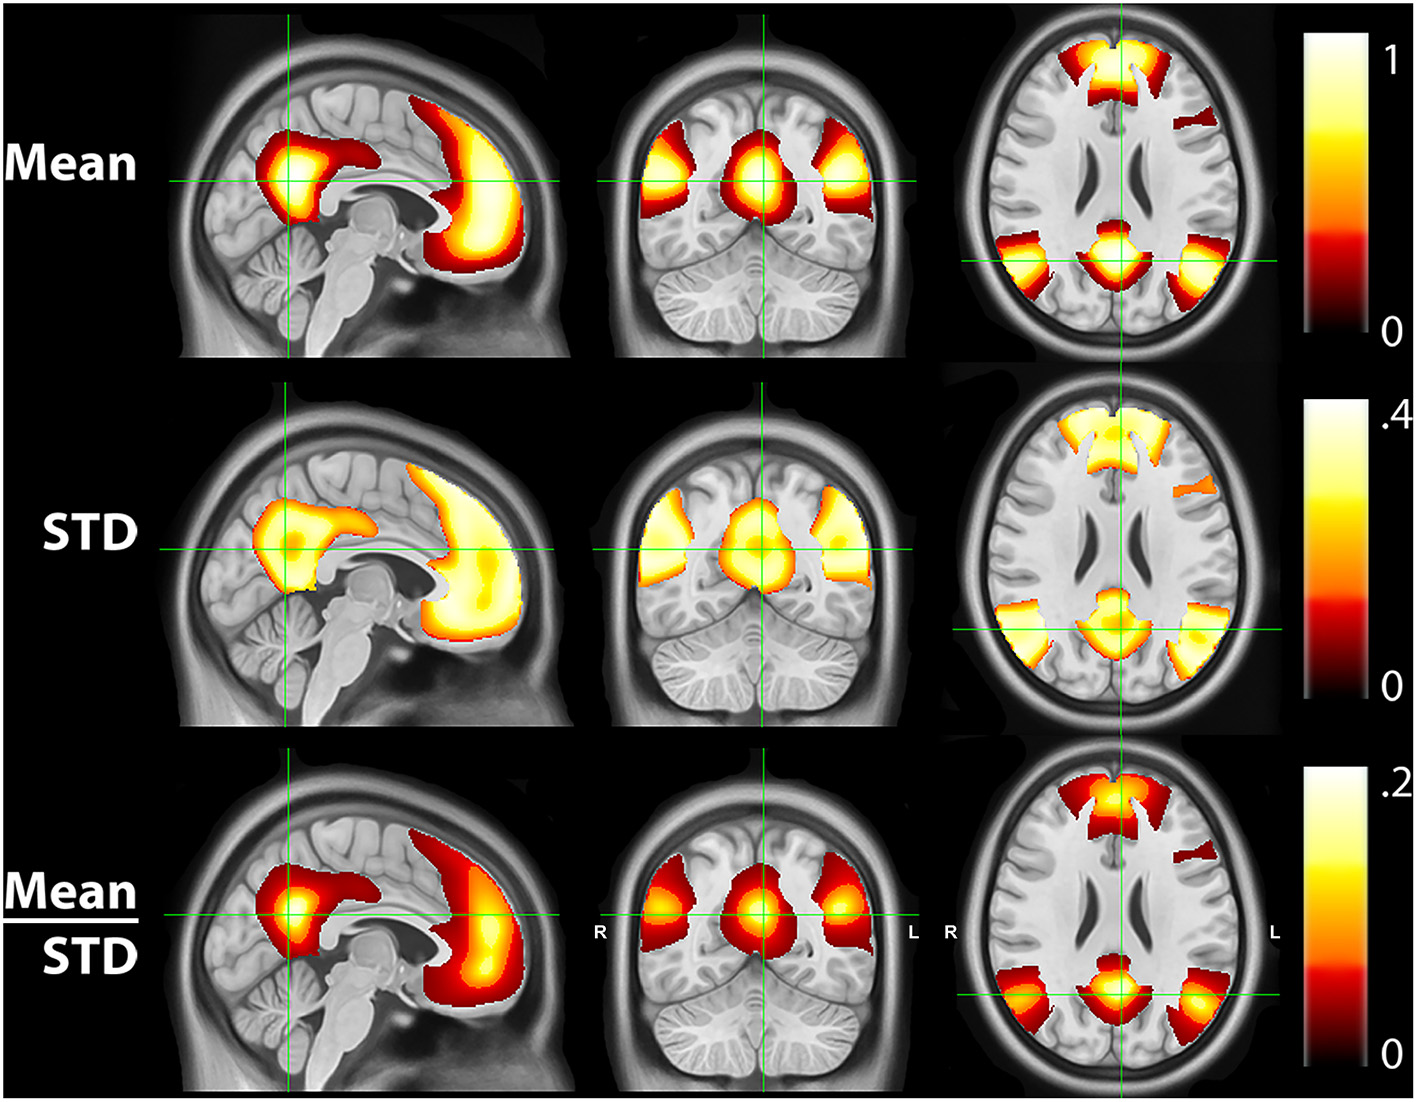

3.3. RSN characterization

Figure 4 shows the mean, STD, and mean/STD probability maps for the DMN (masked based on WTA probabilities from Figure 1). These results show that a large number of voxels show high mean probabilities. However, the STD maps show that the majority of those voxels have a relatively high STD, likely due to individual subject variability and limited signal to noise ratio in the data. Scaling the mean values by the STD, a measure akin to signal to noise ratio, demonstrates higher certainty of RSN membership centrally and the expected uncertainty present at the margins of the WTA regions.

Figure 4

Mean, standard deviation (STD), and mean/STD probability maps for the default mode network (DMN). The mean results show a large number of voxels with high probabilities. STD maps show the majority of voxels have a relatively high STD. When scaling the mean values by the STD, the regions with high relative probabilities becomes significantly smaller.